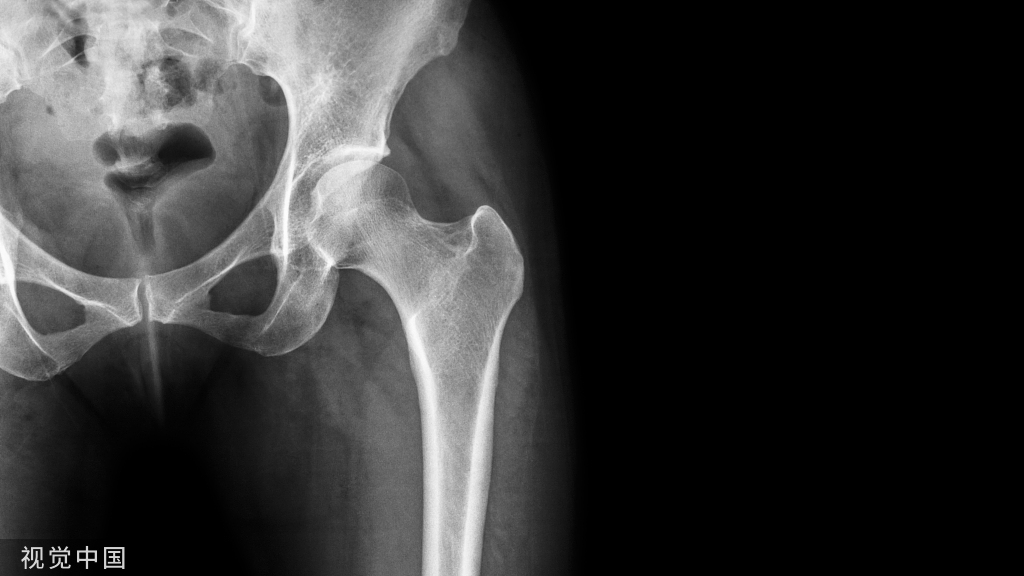

文献中描述了两例骶骨成形术相关骨水泥渗入神经孔的病例,如下图。有一过性 S1 神经炎,在经椎间孔硬膜外注射类固醇后消退。